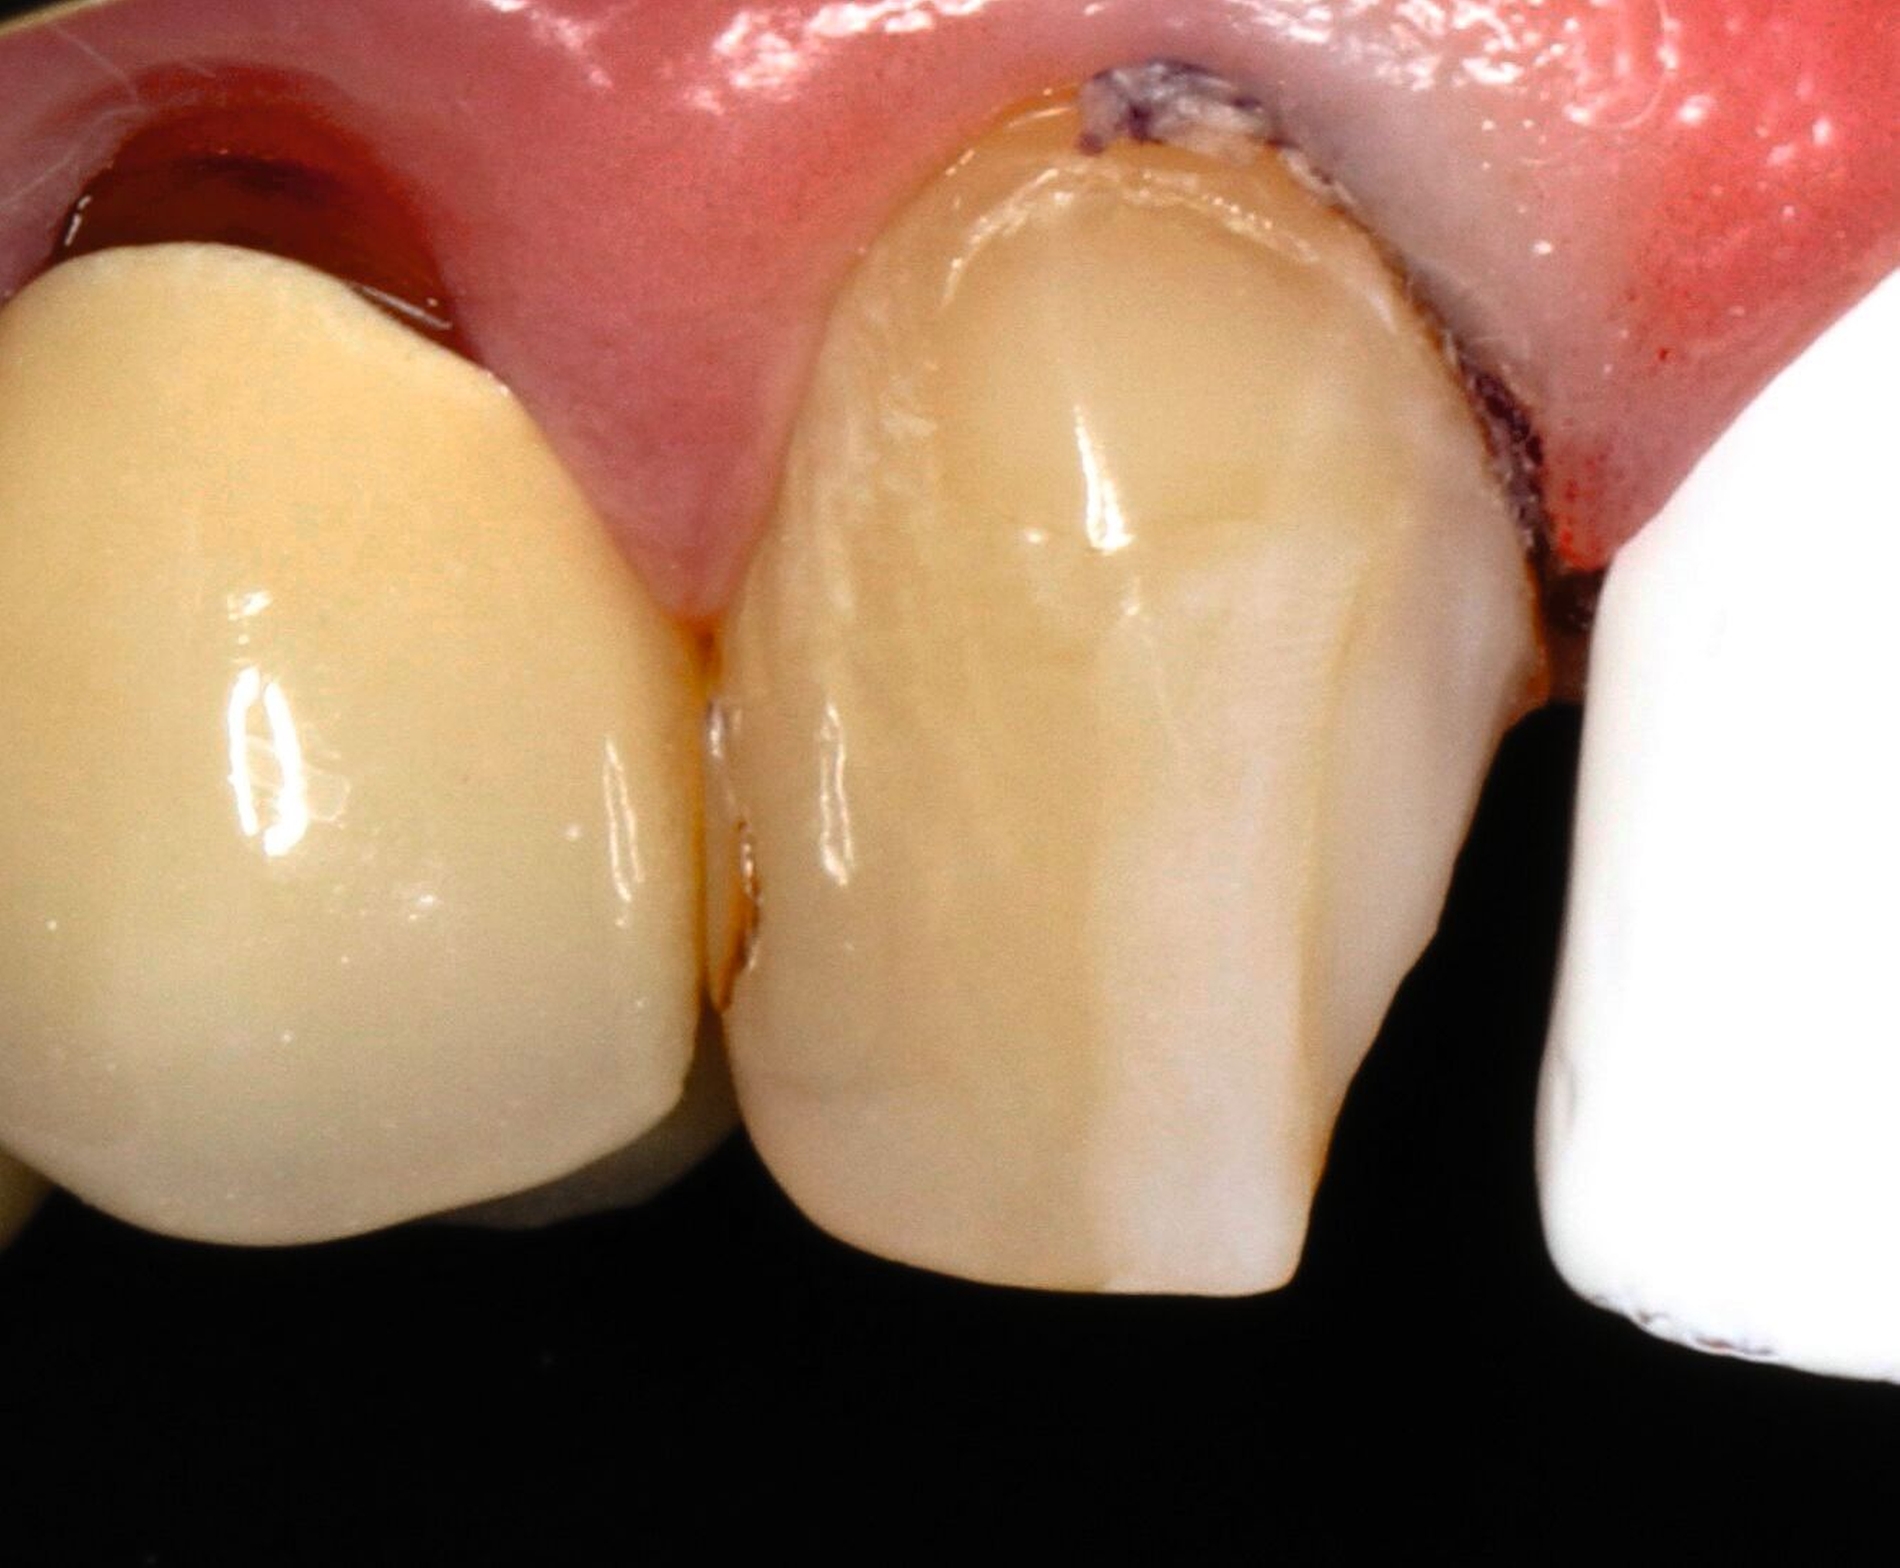

Vor 25 Jahren hatte der Patient ein Frontzahntrauma an Zahn 22 erlitten, der daraufhin mit einer Wurzelspitzenresektion und einer retrograden Amalgamfüllung versorgt worden war (Abbildung 3a). Dabei war die Zahnkrone mit einer keramisch verblendeten Stiftkrone aus Nichtedelmetall rekonstruiert worden, die nun aufgrund von Sekundärkaries insuffizient und gelockert war, jedoch keine Beschwerden verursachte. Klinisch wies der Zahn eine sehr kurze klinische Krone ohne ausreichendes Ferruledesign auf (Abbildung 5a) [Naumann et al., 2018a; Naumann et al., 2018b]. Neben dem Verdacht auf einen obliterierten mittleren Wurzelkanalabschnitt gab es röntgenologisch keinen Hinweis auf apikale Osteolysen oder parodontale Auffälligkeiten (Abbildung 3b). Der Patient entschied sich trotz des erhöhten Zahnhartsubstanzdefekts für den Zahnerhalt durch einen adhäsiv verankerten Kompositaufbau.

Für die restaurative Therapie von Zahn 22 wurde die alte Stiftkrone entfernt und die Stiftbohrung an die neue Indikation angepasst (Abbildungen 5a und 5b). Die Zahnkrone wurde dabei in drei Phasen wiederhergestellt: adhäsives Zementieren eines konfektionierten Glasfaserstifts, Stumpfaufbau und Modellation einer direkten Kompositkrone mit Silikonschlüssel, Frontzahnmatrize für komplexe Situationen und Schneepflugtechnik (Abbildungen 5c bis 5e) [Urkande et al., 2023; Amaro et al., 2021; Frese, 2020; Mannocci et al., 2002; Dimitrouli et al., 2011; Opdam et al., 2003]. Im Röntgenkontrollbild zeigt sich ein suffizienter Stiftaufbau (Abbildung 6).